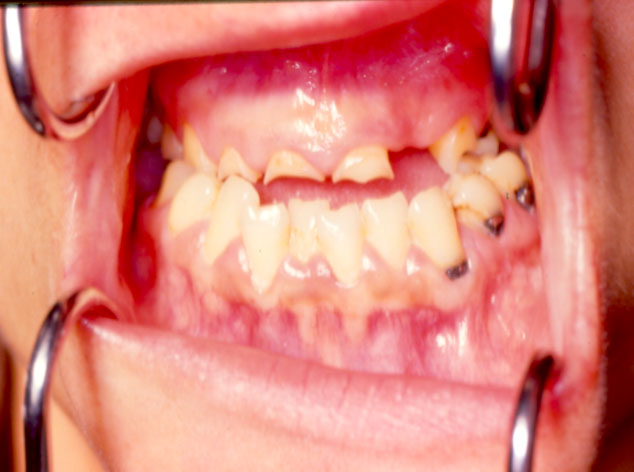

Imagen intraoral del resultado final obtenido después de la cirugía de la osteotomía de Obwegeser, en la que se retruyó la mandíbula aproximadamente tres milímetros; se aprecia la oclusión estable y la corrección de la asimetría que presentaba previamente la paciente.